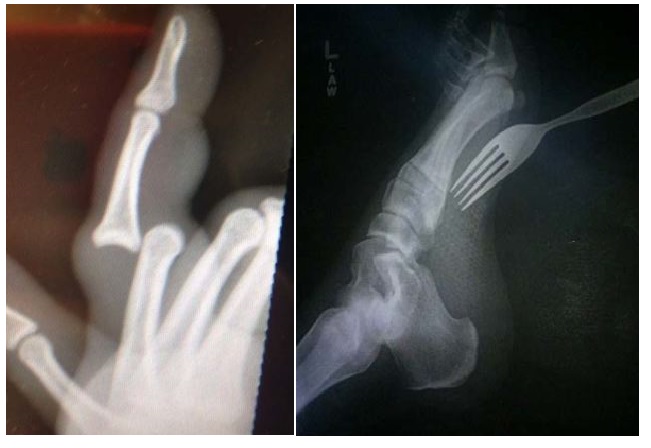

Pokud se vám někdy stal vážnější úraz nebo nehoda, určitě víte jaký to je pocit, když vám musí rentgenovat a prohmatávat zpřeházené nebo popraskané kosti. Ano, není to nic příjemného. Proto tu máme dnes galerii úlovků z rentgenu, které se jen tak nevidí.